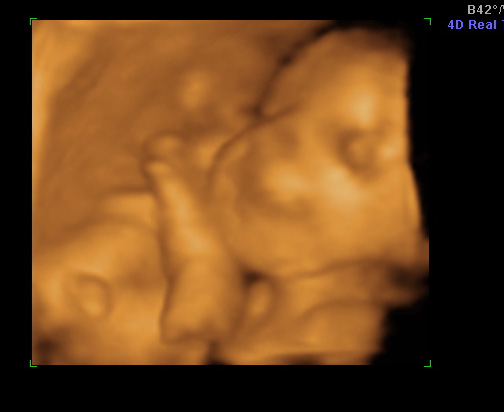

Voltam megint 4D-n. Állítólag 1400g és a mérete 29-30 hetesnek felel meg. Rakok fel képeket.

Kép Kép

A2. képen éppen mosolyog. Olyan jó volt így látni. Lemérték a talpát. Már 5cm. :D